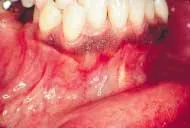

The patient's vital signs were all found to be within normal limits. Extraoral examination of the head and neck region revealed no enlarged or palpable lymph nodes. Intraoral examination revealed a small, bony enlargement of the alveolar bone between the mandibular canine and incisor (see photo).

Based on this clinical finding, a periapical radiograph of the region was exposed. The film revealed a well-defined, ovoid radiolucency located between the roots of teeth #26 and #27 (see film). The teeth adjacent to the swelling were pulp-tested for vitality, and both tested vital. The patient was referred to an oral surgeon for biopsy and removal of the lesion. Microscopic examination revealed a cyst lined by stratified squamous epithelium with nodular thickenings and a thin, fibrous-connective tissue wall.